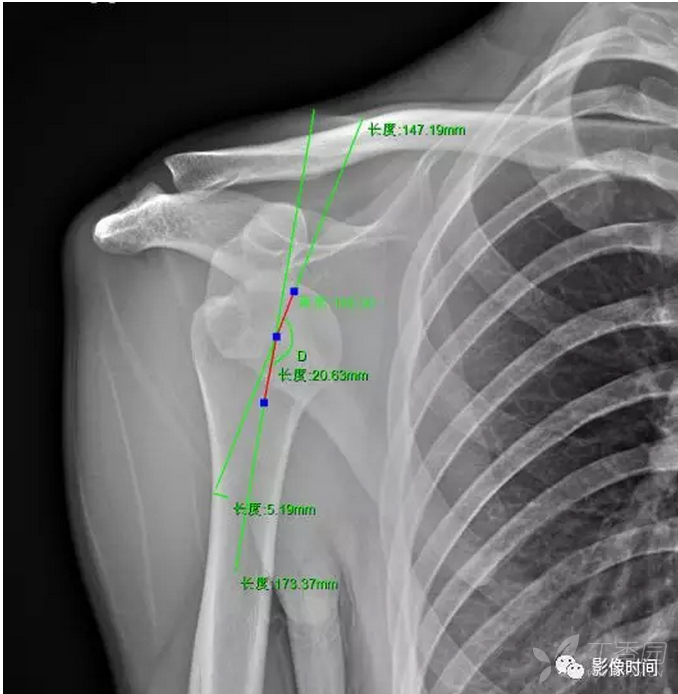

切换新版 >> 不再显示 × 肩关节间隙 4 mm 肱骨颈干角 肱骨干中线

1,肩关节活动角度;2,肱骨颈干角;3,肱骨头后倾角;4,肱骨远端前倾角;5